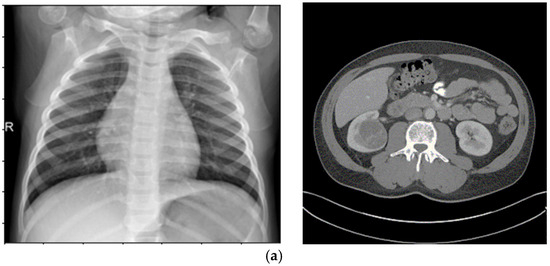

Enhancing Medical Image Segmentation and Classification Using a Fuzzy-Driven Method

Automated analysis for tumor segmentation and illness classification is hampered by the noise, low contrast, and ambiguity that are common in medical pictures. This work introduces a new 12-step fuzzy-based improvement pipeline that uses fuzzy entropy, fuzzy standard deviation, and histogram spread functions [...] Read more.

Automated analysis for tumor segmentation and illness classification is hampered by the noise, low contrast, and ambiguity that are common in medical pictures. This work introduces a new 12-step fuzzy-based improvement pipeline that uses fuzzy entropy, fuzzy standard deviation, and histogram spread functions to enhance picture quality in CT, MRI, and X-ray modalities. The pipeline produces three improved versions per dataset, lowering BRISQUE scores from 28.8 to 21.7 (KiTS19), 30.3 to 23.4 (BraTS2020), and 26.8 to 22.1 (Chest X-ray). It is tested on KiTS19 (CT) for kidney tumor segmentation, BraTS2020 (MRI) for brain tumor segmentation, and Chest X-ray Pneumonia for classification. A Concatenated CNN (CCNN) uses the improved datasets to achieve a Dice coefficient of 99.60% (KiTS19, +2.40% over baseline), segmentation accuracy of 0.983 (KiTS19) and 0.981 (BraTS2020) versus 0.959 and 0.943 (CLAHE), and classification accuracy of 0.974 (Chest X-ray) versus 0.917 (CLAHE). A classic CNN is trained on original and CLAHE-filtered datasets. These outcomes demonstrate how well the pipeline works to improve image quality and increase segmentation/classification accuracy, offering a foundation for clinical diagnostics that is both scalable and interpretable. Full article